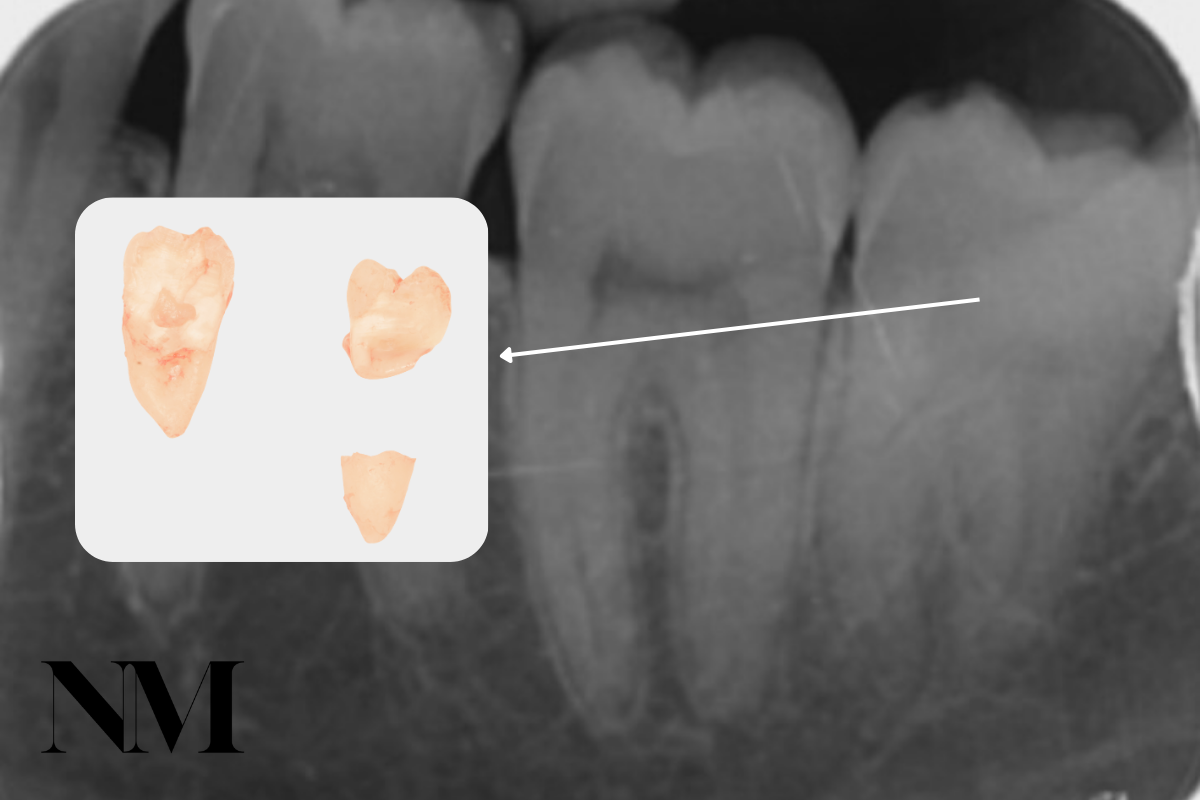

Surgical Extractions

A surgical extraction is required when teeth are broken at the gum line, impacted, or not readily accessible. These procedures are carried out with precision and care, often involving small incisions and sectioning of the tooth to allow for safe removal.

I use minimally invasive techniques to reduce discomfort and speed up recovery.